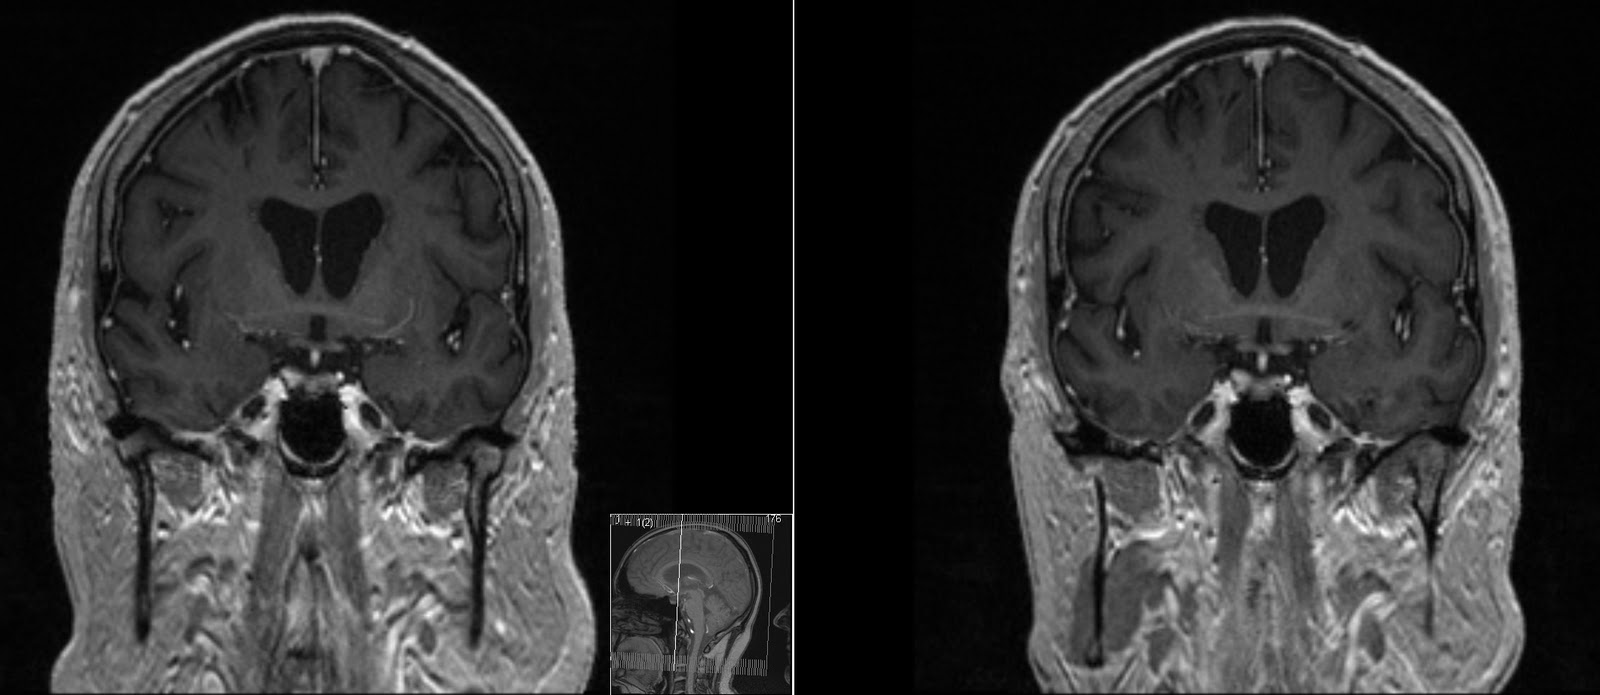

MRI images of patients with Alzheimer’s disease. Temporal horn width Anterior Horn Disease Mri Amyotrophic lateral sclerosis is a relentlessly progressive neurological disorder characterized by the death of upper motor neurons (betz cells in the cortex) and anterior horn. Flexion cervical mr imaging is a very useful investigation in diagnosing hirayama disease. Emg/ncs, serum and urine electrophoresis,. Incomplete spinal cord syndromes are reviewed, with descriptions of the relevant spinal cord anatomy and common causes. Anterior Horn Disease Mri.